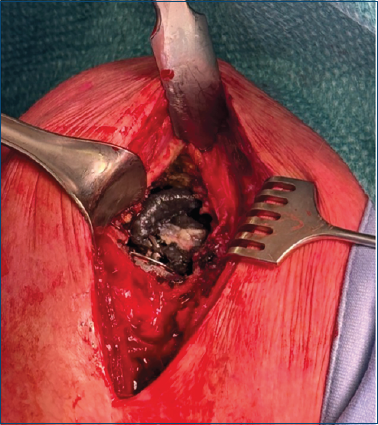

La glenosfera, la vite di bloccaggio, il connettore e l’inserto omerale sono stati rimossi (Fig. 4). All’esame dei componenti, è stata identificata la rottura dell’anello di connessione della glenosfera come causa della mobilizzazione. L’area è stata abbondantemente irrigata e sono state prelevate colture intraoperatorie.

Figura 4. Immagine intraoperatoria. Glenosfera, vite di bloccaggio, connettore e inserto omerale rimossi. L’anello di connessione è rotto e presenta metallosi al suo interno.